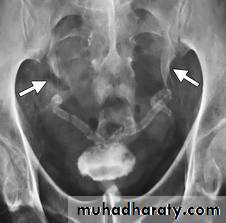

Schistosomiasis

Infestation by s.hematobium

Calcification is most important feature, mainly in bladder & lower ureters , but may involve whole ureters .

In early stage inflammation may cause cobble stone appearance.

Bladder capacity not affected.

Ddgx of bladder calcification :

1. schistosomiasis .

2.tumor , TB, …